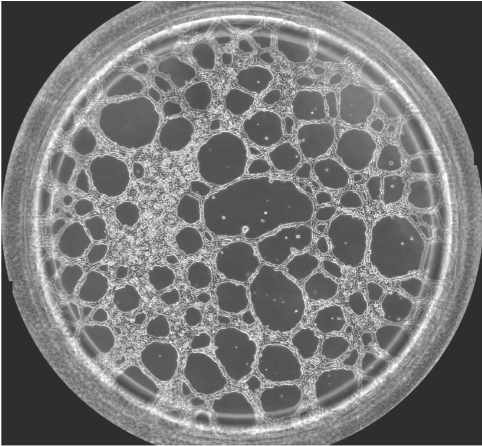

圖一 血管生成鏡檢圖

無論原發(fā)性腫瘤還是繼發(fā)性腫瘤,一旦生長直徑超過1~2 mm,都會有血管生成。這是由于腫瘤細(xì)胞自身可分泌多種生長因子,誘導(dǎo)血管生成。多數(shù)惡性腫瘤的血管生成密集且生長迅速。因此,血管生成在腫瘤的發(fā)展轉(zhuǎn)移過程中起到重要作用,抑制這一過程將能明顯阻止腫瘤組織的發(fā)展和擴(kuò)散轉(zhuǎn)移。于是體外的血管生成實(shí)驗(yàn)就能很好的模擬腫瘤的血管發(fā)生過程,并且適合研究藥物對這一過程的影響實(shí)驗(yàn)。本實(shí)驗(yàn)以HUVEC細(xì)胞為例,介紹這一實(shí)驗(yàn)的詳細(xì)過程。